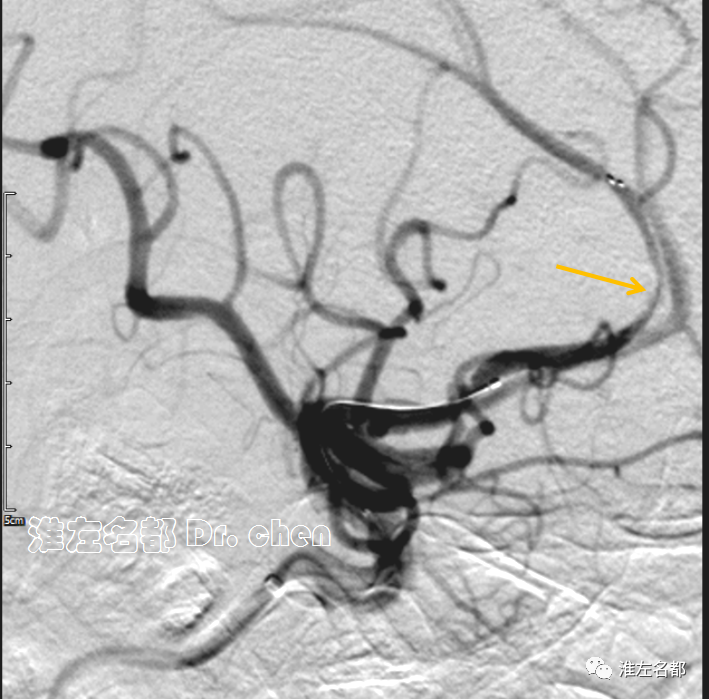

△经微导管释放取栓支架 S AB 4*20mm,造影:闭塞再通,局部管腔狭窄(橙箭)。

因路径迂曲,操作极其艰难,穿刺成功-第一次释放取栓支架已经花费了约60分钟。考虑到路径迂曲,回收支架出血风险高;如果第一次取栓未能开通闭塞,估计其后的操作可能还要花费很长时间,患者可能难以耐受,且取栓获益可能性也会降低。

△30分钟后造影:左侧大脑前动脉前向血流良好,A3段局部中度狭窄(橙箭)

静推欣维宁15ml,7ml/h维持,30分钟后造影可见左侧大脑前动脉前向血流良好,A3段局部中度狭窄,解脱取栓支架。